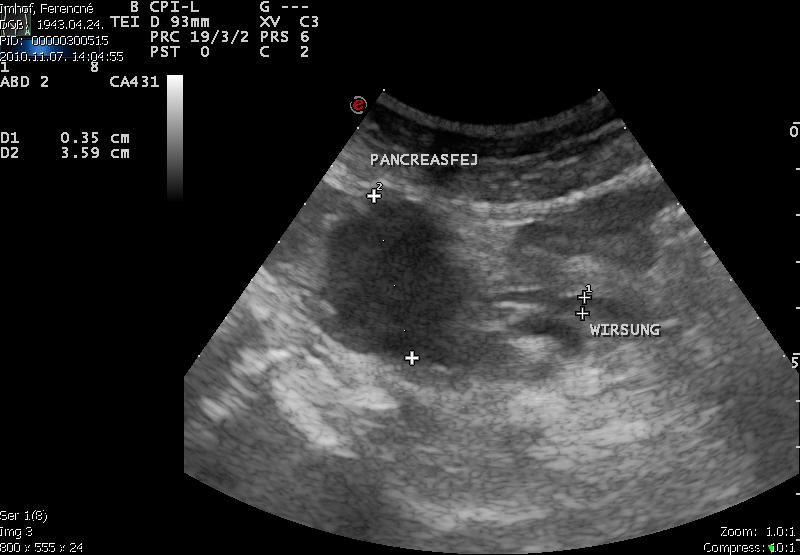

Idős hölgy sárgasággal

- Pancreas